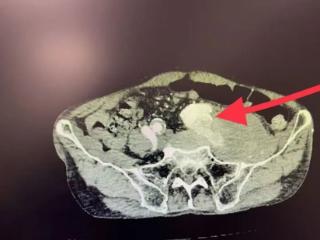

八旬老人突发腿肿,竟是“动脉炸弹”破裂!北大人民青岛医院血管外科顺利拆弹保平安